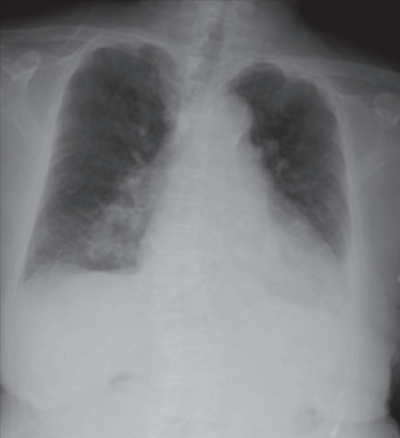

尿所見:蛋白+、糖(-)、潜血(-)。血液所見:Hb 7.2 g/dL。血液生化学所見:総ビリルビン 2.0 mg/dL、AST 98 U/L、ALT 86 U/L、γ-GT 60 U/L(基準 8 ~ 50)、尿素窒素 20 mg/dL、クレアチニン 1.14 mg/dL、Na 128 mEq/L、K 4.8 mEq/L、Cl 98 mEq/L、TSH 197 μU/mL(基準 0.2~4.0)、FT4 0.02 ng/dL(基準 0.8~2.2)。心電図で徐脈と四肢誘導での低電位を認める。胸部エックス線写真を別に示す。